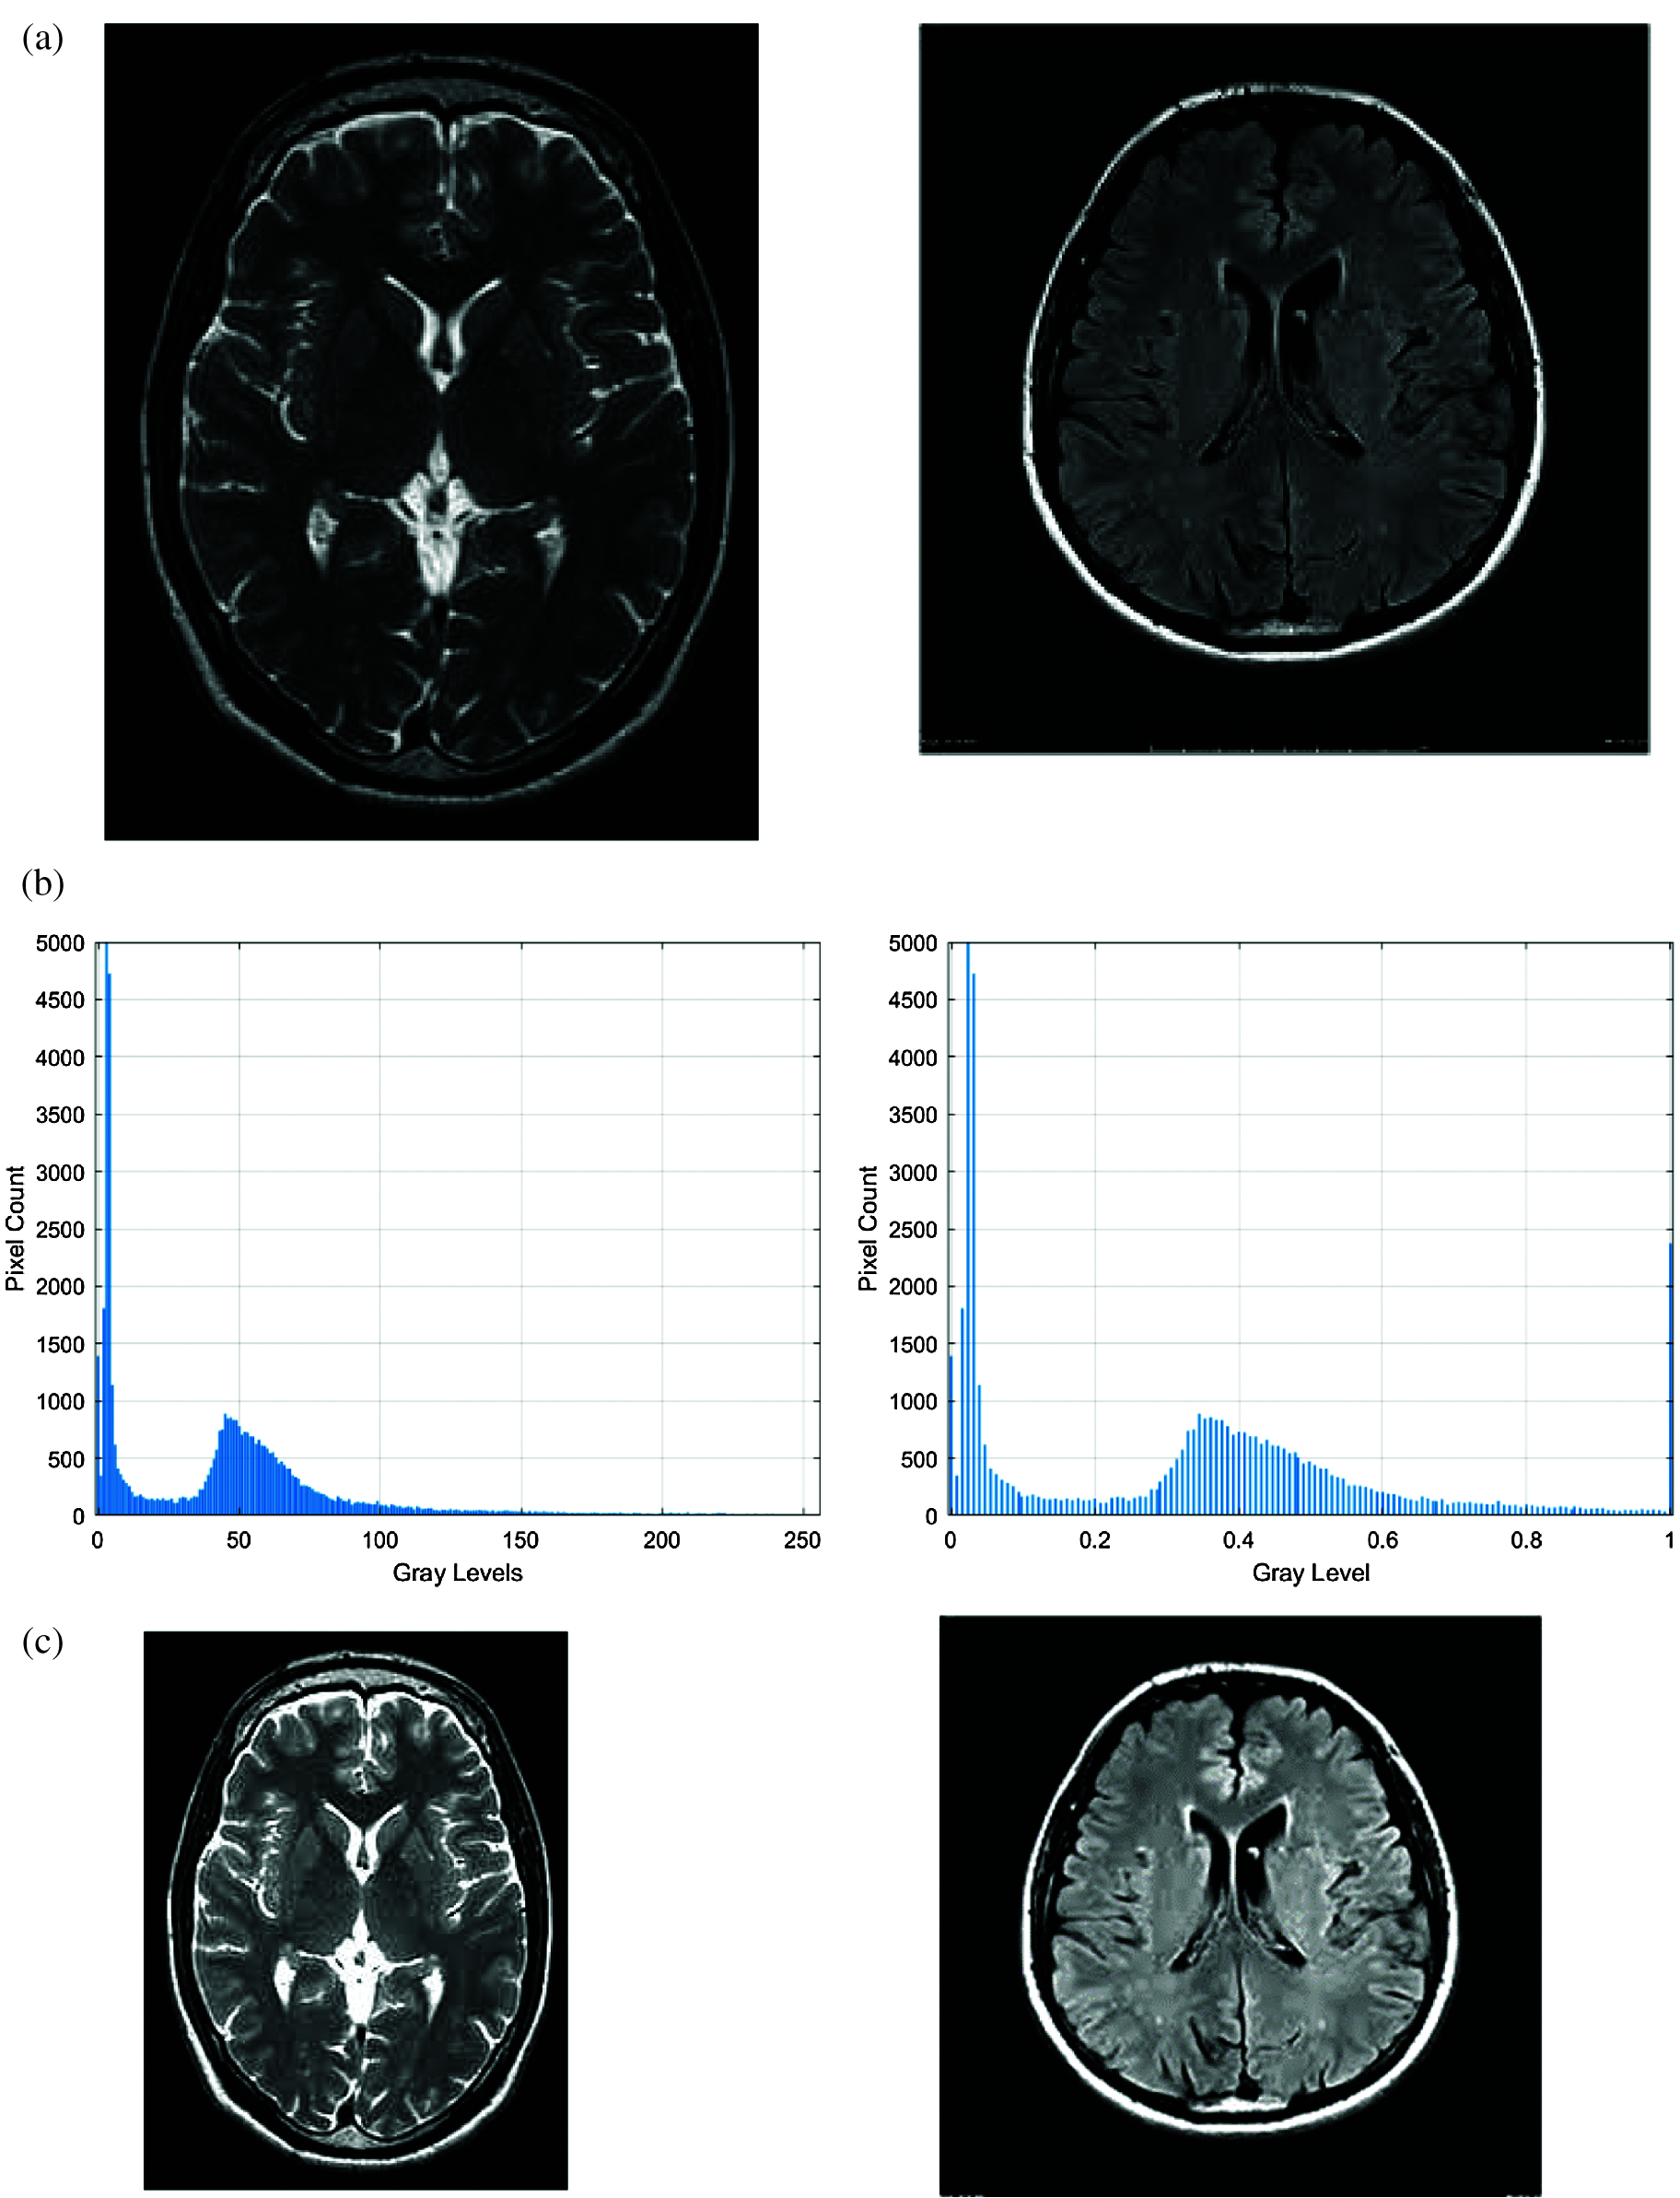

The histogram analysis of the input and the enhanced images are shown in Figs. 2b, 2d respectively. It is apparent from Fig. 2b that the probability distribution of the input image pixels looks compact, while the probability distribution of the pixels in the enhanced image Fig. 2d looks more scattered. This implies that the image's quality and contrast have been improved.

Figure 2: Sample output of the proposed algorithm along with histogram analysis. (a) Input image, (b) Histogram detail of input image, (c) Enhanced image, (d) Histogram detail of enhanced image